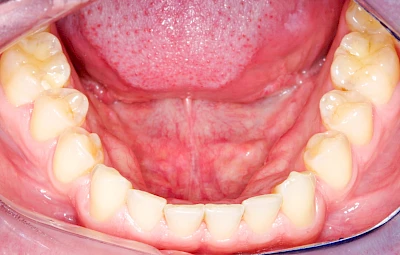

Knochenschwund (Atrophie)

Gehen die Zähne verloren, baut häufig auch der Kieferknochen ab (Knochenschwund). Die Geschwindigkeit und das Ausmaß des Knochenschwundes ist von vielen Faktoren abhängig. Neben der genetischen Veranlagung spielen auch Überbelastungen in Folge, z. B. bei ständigem Knirschen oder Pressen, eine Rolle. Auch wenn Zahnprothesen Tag und Nacht getragen werden, kann die ständige Belastung der Schleimhäute und des Knochens den Knochenschwund beschleunigen.

Aber Achtung: Manche Menschen fühlen sich ohne Zahnprothesen unwohl. Zudem kann es passieren, dass Zahnprothesen (wenn noch eigene Zähne vorhanden sind) nicht mehr passen. Dies gilt vor allem dann, wenn diese Zahnprothesen nicht nur über Nacht, sondern für einen längeren Zeitraum nicht mehr getragen werden.

In jedem Fall sagen die Betroffenen, dass es sich ein paar Minuten komisch anfühlt, wenn sie die Zahnprothesen über Nacht aus dem Mund nehmen und dann morgens wieder einsetzen. Das ist normal und liegt daran, dass die Schleimhäute sich wieder regenerieren. Das ist gut für die Schleimhäute und Knochen im Bereich der Kiefer. Wir gehen ja auch nicht mit Schuhen ins Bett!